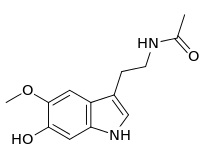

| 6-Hydroxymelatonin | Animals | 5-OCH3, 6-OH | H | O=C-CH3 | N-[2-(6-Hydroxy-5-methoxy-1H-indol-3-yl)ethyl]acetamide | 2208-41-5 |